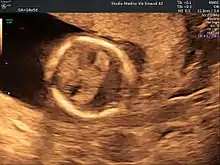

Holoprosencephaly (HPE) is a cephalic disorder in which the prosencephalon (the forebrain of the embryo) fails to develop into two hemispheres. Normally, the forebrain is formed and the face begins to develop in the fifth and sixth weeks of human pregnancy. The condition also occurs in other species.

When the embryo's forebrain does not divide to form bilateral cerebral hemispheres (the left and right halves of the brain), it causes defects in the development of the face and in brain structure and function.